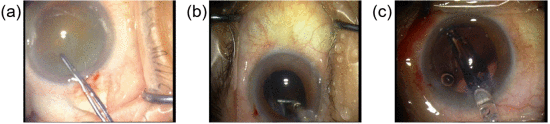

③PhacoQ数据集示例,器械和组织交互非常不明显:

quintuple adj./det.五倍的;由五部分(或人、群体)构成的;五方面的 v.(使)成为五倍 n.五倍量;〈罕〉五个一套

①白内障手术视频数据集PhacoQ,包含20个帧率为1 fps的手术视频。每帧的注释包括仪器和组织的位置,以及仪器、组织和动作的类型。注释包含12种仪器、12种组织和15种作用类型,总共产生32种交互方式。PhacoQ数据集随机分为包含12个视频的训练集、包含4个视频的验证数据集和包含4个视频的测试集。